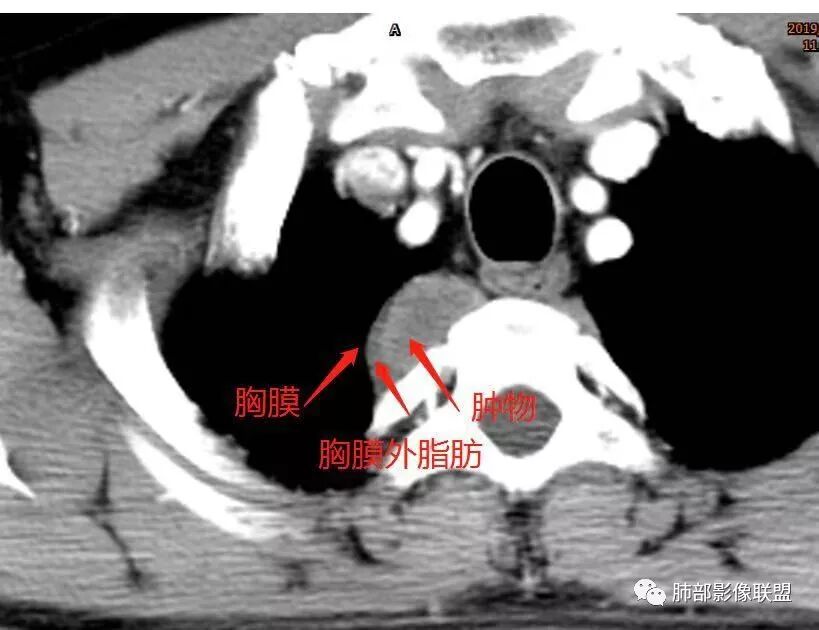

小编回顾性分析

这个病例定位肺外没问题,病灶呈宽基底,见明显的胸膜掀起征,定位胸膜或右后纵隔来源,而且肿块提示肋间动脉穿行,脏层胸膜来源可能性不大(脏层胸膜由肺动脉及支气管动脉供血),那就是壁层胸膜跟纵隔来源,但是图像上有2个层面是胸膜外间隙有受压推移,所以壁层胸膜来源也不考虑;病灶是渐进性强化,常见的就是间叶来源含有梭形细胞的软组织肿瘤跟后纵隔常见的神经源性肿瘤鉴别,那如何在后纵隔的大山里拨开云雾找到我们想要的答案呢?那小编在这里先理出几个问题: